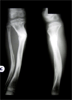

Infected non-union tibia in a 10year old child

Pre

Op

Xrays : Chroin osteomyelitis with bone gap proximally